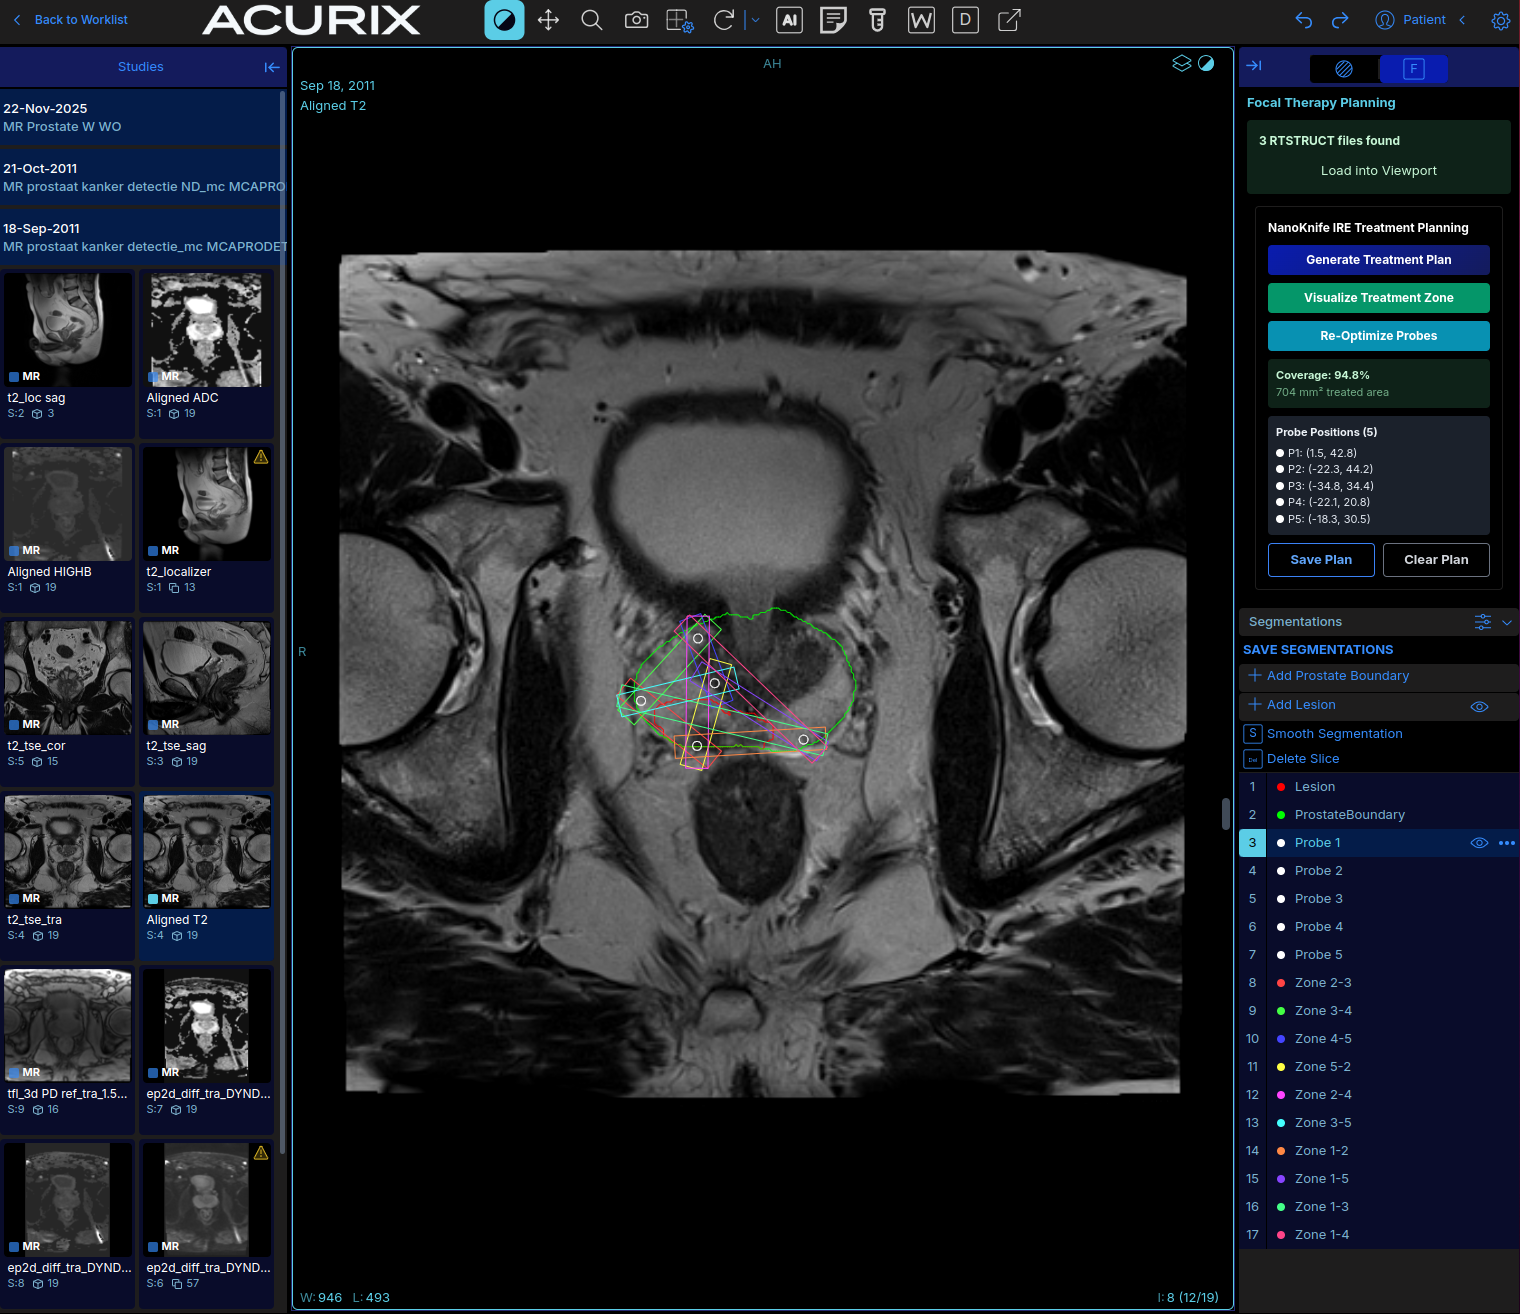

Focal Therapy Planning

NanoKnife IRE focal therapy treatment planning with probe placement and treatment zones

NanoKnife IRE (irreversible electroporation) treatment planning directly within the imaging viewer. Using the AI-generated prostate boundary and lesion segmentation as inputs, the system computes optimal probe placement to maximize lesion coverage with a safety margin.

Five probes are placed across four treatment phases, generating 10 treatment zones. Coverage fraction is computed in real time. Probes can be manually adjusted with zones recomputing automatically. The final plan is saved as a multi-slice DICOM RTSTRUCT for integration with treatment delivery systems.